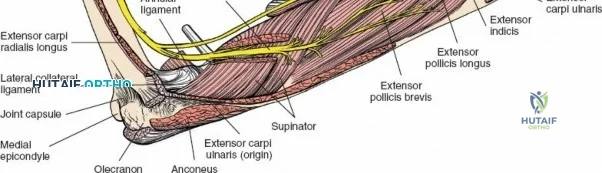

The Internervous Planes of the Forearm

The anterior approach to the radius is an elegant example of utilizing true internervous planes to achieve deep exposure without denervating musculature. Distally, the internervous plane lies between the brachioradialis muscle (innervated by the radial nerve) and the flexor carpi radialis muscle (innervated by the median nerve). Proximally, the plane transitions to lie between the brachioradialis (radial nerve) and the pronator teres muscle (median nerve). Exploiting this plane allows the surgeon to mobilize the entire lateral muscular compartment (the "mobile wad" comprising the brachioradialis, extensor carpi radialis longus, and extensor carpi radialis brevis) away from the anterior flexor compartment.

The Posterior Interosseous Nerve (PIN)

The posterior interosseous nerve is the single most important structure left vulnerable during exposure of the proximal radius. A branch of the radial nerve, the PIN dives into the supinator muscle through the Arcade of Frohse. It travels obliquely and spirally around the radial neck and proximal shaft within the substance of the supinator. In approximately 25% of patients, the nerve comes into direct contact with the posterior periosteum of the radial neck. Therefore, any blind placement of retractors around the posterior aspect of the proximal radius is strictly contraindicated, as it can easily crush the nerve against the bone, resulting in devastating loss of finger and thumb extension.

Vascular Anatomy and the Recurrent Radial Leash

The radial artery runs distally through the forearm, initially lying deep to the brachioradialis muscle before becoming more superficial in the distal third. Just distal to the elbow joint, the radial artery gives off a complex network of vessels known as the recurrent radial artery leash (the "leash of Henry"). These vessels branch laterally to supply the brachioradialis and the mobile wad. To successfully mobilize the brachioradialis laterally and access the proximal radius, this entire leash of vessels must be meticulously isolated, ligated, and divided. Failure to do so will tether the brachioradialis, prevent adequate exposure, and risk severe postoperative hematoma from avulsed vessels.